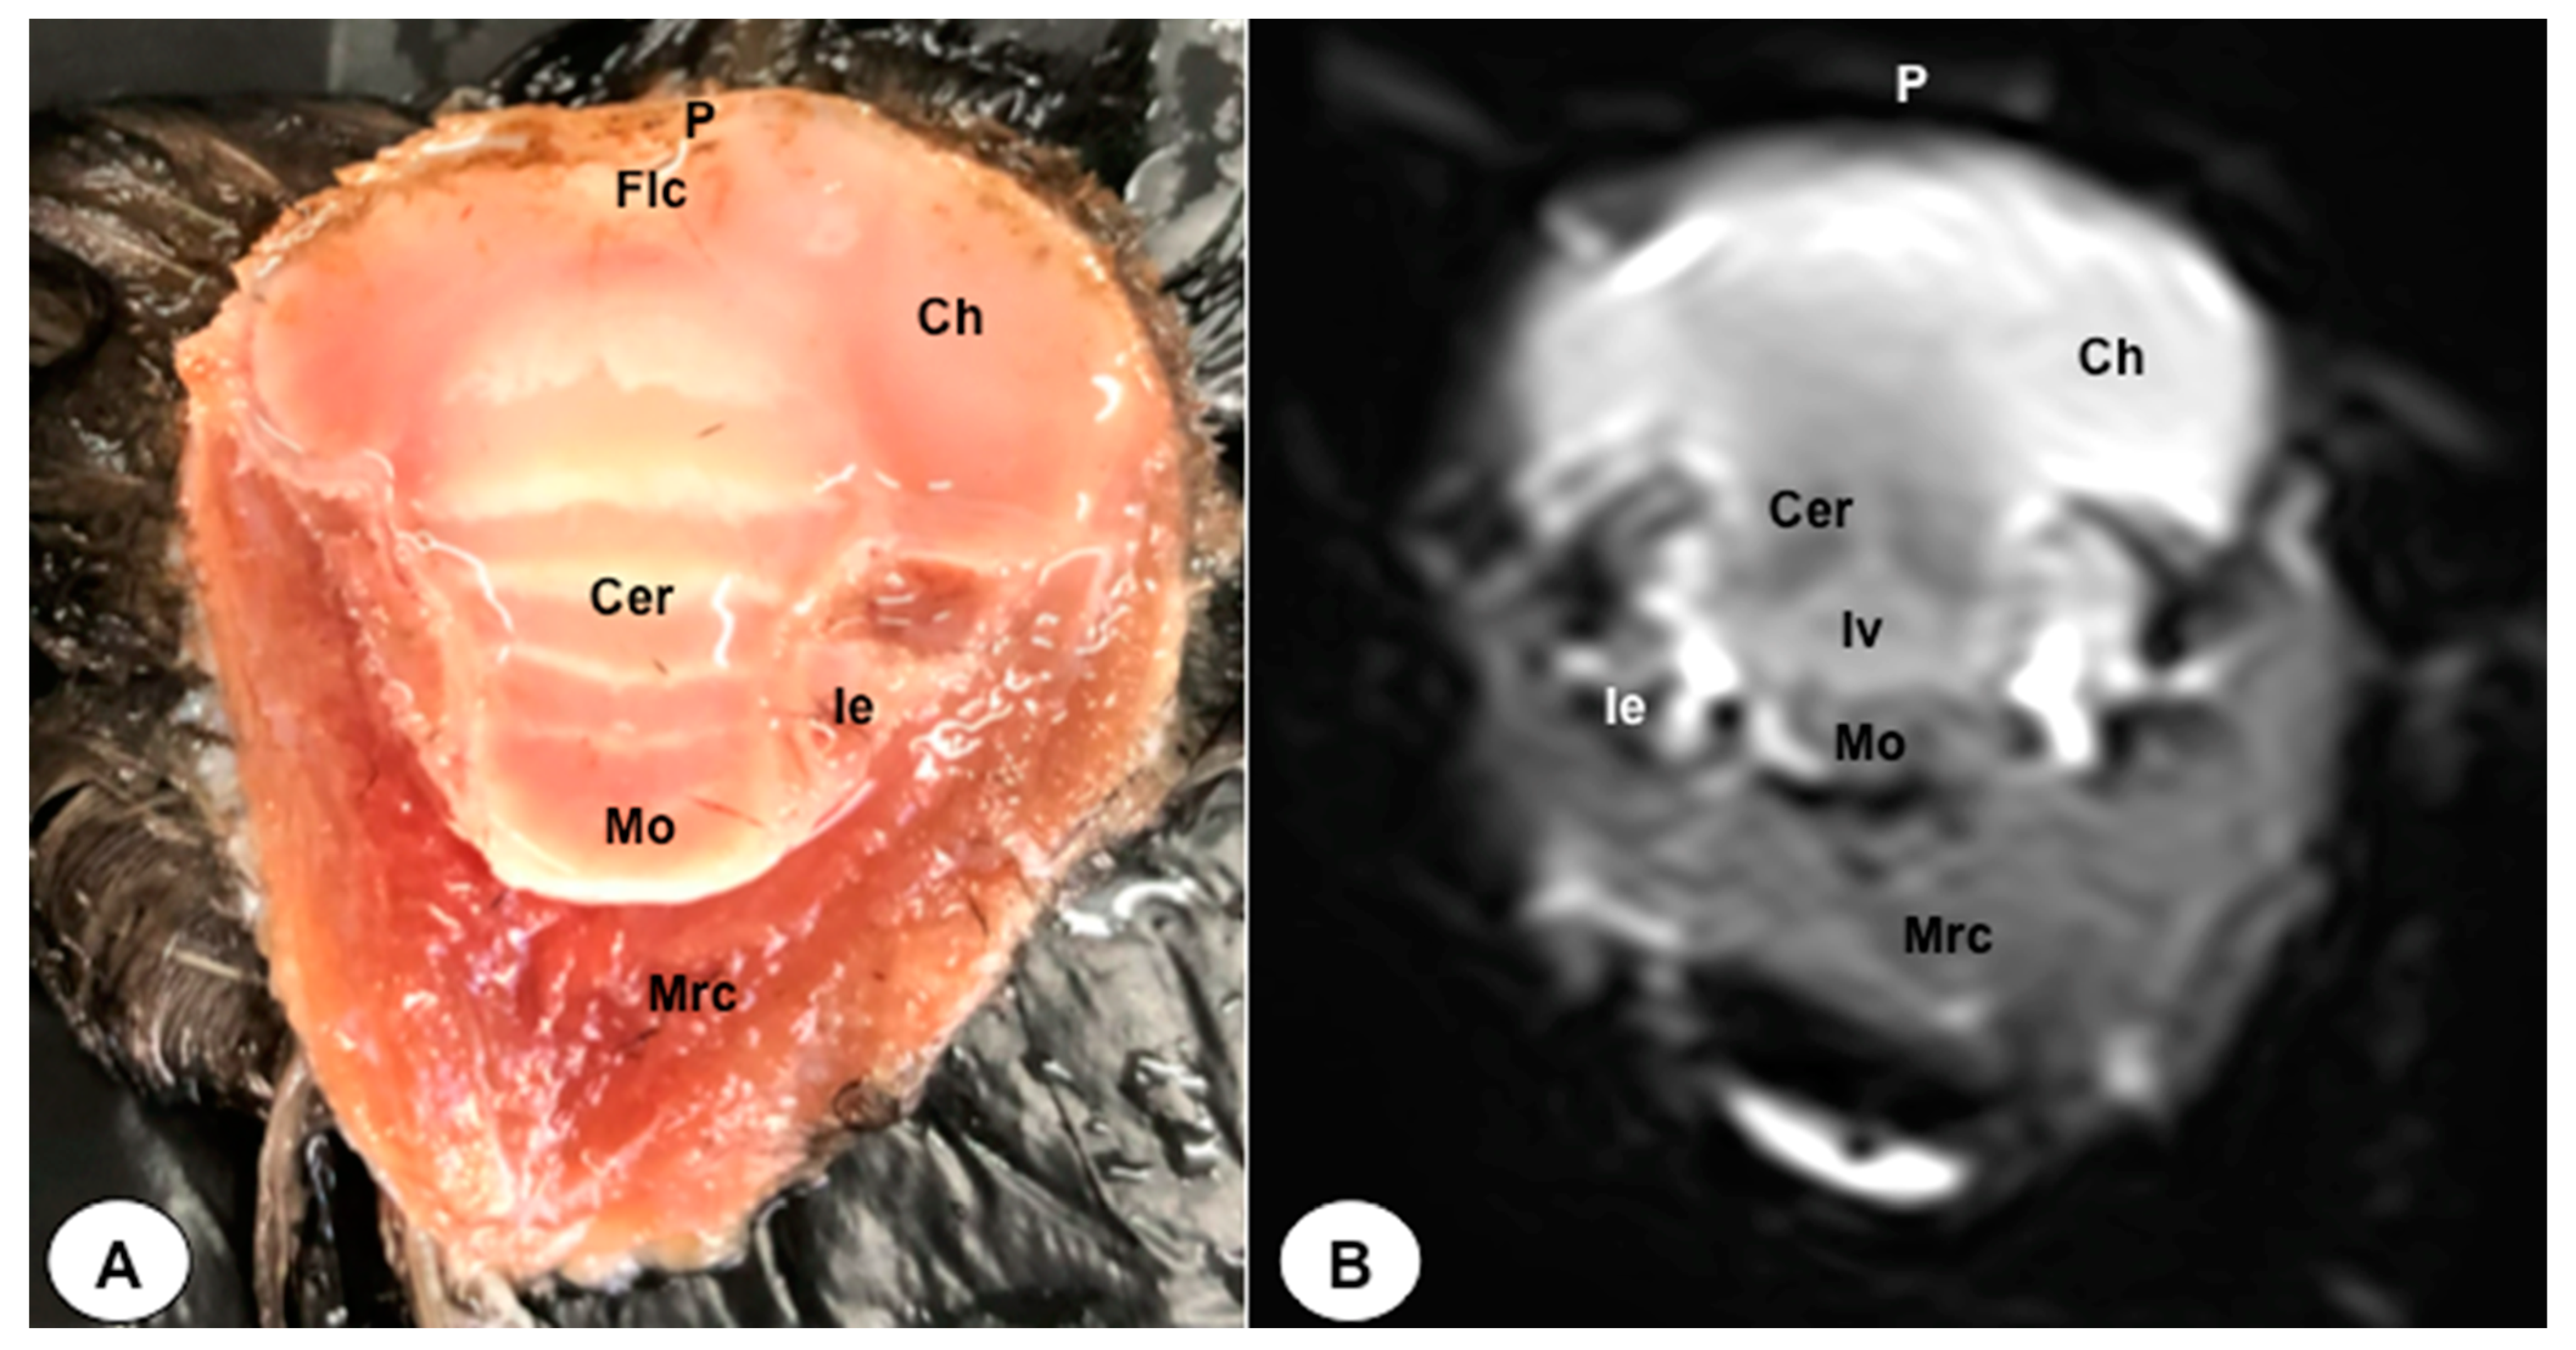

3.1. Anatomical Sections

3.2. Magnetic Resonance Imaging (MRI)